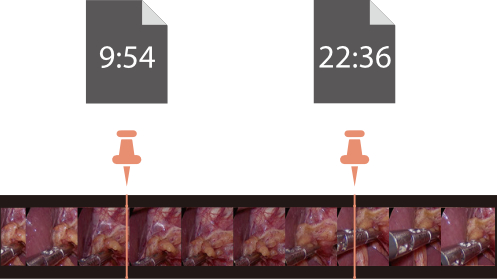

Built-in USB Recording

The built-in USB recording starts with one click, and the high-quality video will be saved as Full HD version as predefined.

With bookmark function, it is convenient for video record review and post-editing.